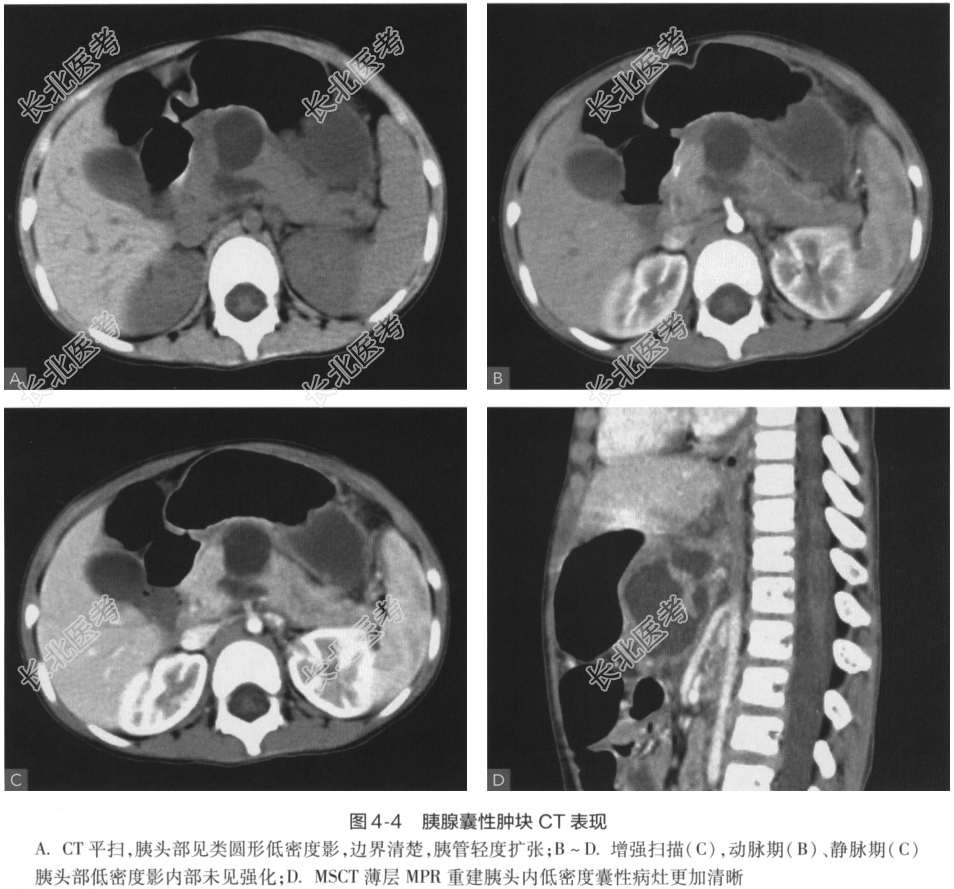

- [材料题] 患儿,男,11岁。呕吐2天,伴腹痛、发热半天。B超:腹腔积液,肝、脾未见明显异常。体格检查全腹柔软,麦氏点压痛阳性,反跳痛可疑,腹部未触及明显包块。实验室检查:血淀粉酶:133U/L(30~110U/L),尿淀粉酶>1200U/L;WBC 16.9×10⁹/L;N 81%。影像学检查: